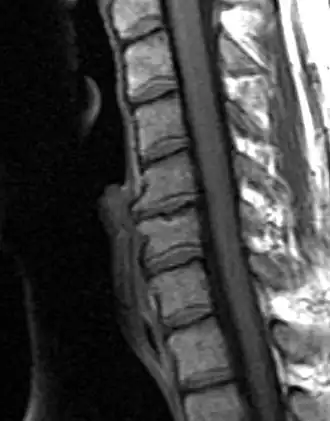

| Degenerated disc between C5 and C6 (vertebra at the top of the picture is C2), with osteophytes anteriorly (to the left) on the lower portion of the C5 and upper portion of the C6 vertebral body. | |